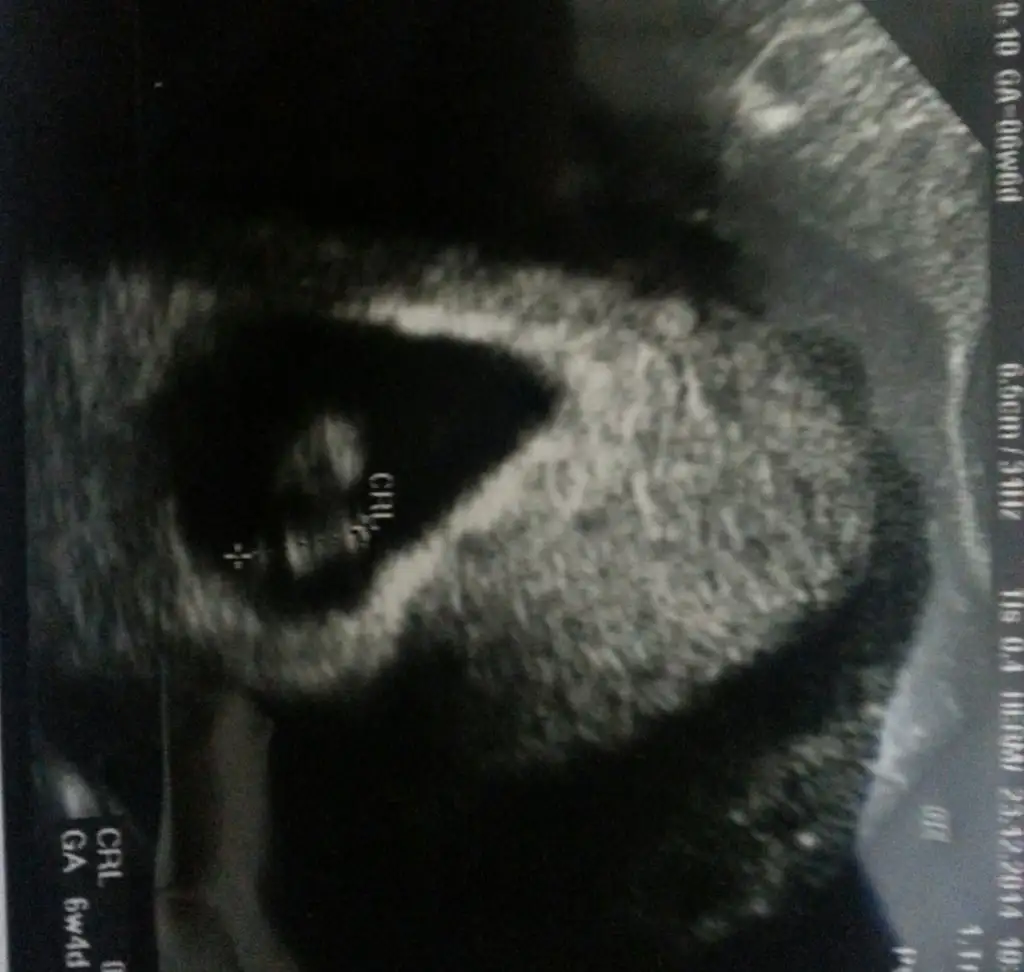

Bu da benim pirincim kizlar....icime hep kiz doguyor ama oncelikle tabiki Allah hayirli saglikli olmasini nasip etsin...

Benim kizimin kesesi ilk gorundugunde kagidi elime alip baktigimda soldaydi 7 haftalikken iyice sagdaydi ultrason kagidinda. Bu kez kesesi sagdaydi 7 haftalikken soldaydi ama buna da kiz dedi dr yani pek guvenemiyorum ben bu tahminlere.